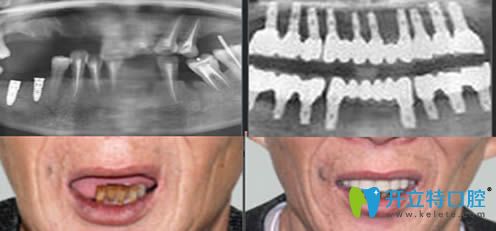

重慶皇仕口腔半口牙種植案例效果前后對(duì)比:

顧客:王先生

牙齒狀況:上牙及部分下牙缺失

治療方案:激光無(wú)痛即刻種植技術(shù)

完成時(shí)間:3小時(shí)

種植感言:3個(gè)小時(shí)就解決了多年的缺牙問(wèn)題,顯年輕不說(shuō),關(guān)鍵是能和年輕時(shí)候一樣吃東西了,對(duì)效果非常滿意。